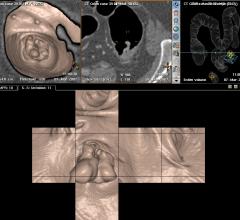

While active surveillance is often recommended for patients with nonaggressive prostate cancer to reduce unnecessary treatment, the challenge for clinicians is to monitor and distinguish early-stage tumors from advanced cancers.